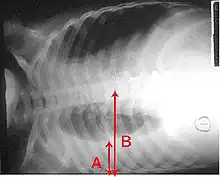

An X-ray showing a chest lying horizontally. The lower black area, which is the right lung, is smaller with a whiter area below it of a pulmonary effusion. Red arrows indicate size.

A pleural effusion: as seen on chest X-ray. The A arrow indicates fluid layering in the right chest. The B arrow indicates the width of the right lung. The volume of the lung is reduced because of the collection of fluid around the lung.

In pneumonia, a collection of fluid may form in the space that surrounds the lung.[139] Occasionally, microorganisms will infect this fluid, causing an empyema.[139] To distinguish an empyema from the more common simple parapneumonic effusion, the fluid may be collected with a needle (thoracentesis), and examined.[139] If this shows evidence of empyema, complete drainage of the fluid is necessary, often requiring a drainage catheter.[139] In severe cases of empyema, surgery may be needed.[139] If the infected fluid is not drained, the infection may persist, because antibiotics do not penetrate well into the pleural cavity. If the fluid is sterile, it must be drained only if it is causing symptoms or remains unresolved.[139]